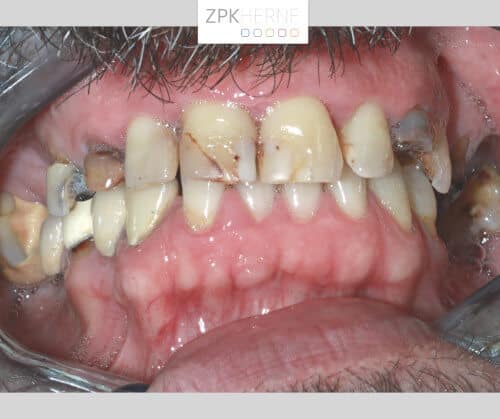

Über ein Jahrzehnt lang hat die Furcht vor dem Behandlungsstuhl unseren Patienten von dem dringend notwendigen Zahnarztbesuch abgehalten. Dabei leidet er fast schon ebenso lange unter einem nicht voll funktionsfähigen Gebiss: Seit mehreren Jahren fehlen ihm im Unter- sowie im Oberkiefer jeweils ab dem Eckzahn einige Zähne. Außerdem ist die Bisshöhe abgesackt, das heißt seit Jahrzehnten knirscht sich der Patient die Zahnsubstanz herunter. Das führt unter anderem dazu, dass er nicht mehr vernünftig essen kann. Hierfür wünscht er sich eine neue festsitzende Versorgung mittels Implantate.

Nach der gründlichen Anamnese werden aktuelle 3D-Aufnahmen der Gebisssituation erstellt. Dabei kommt das Team um Herrn Dr. Mintert zu den folgenden Ergebnissen und Handlungsschritten: